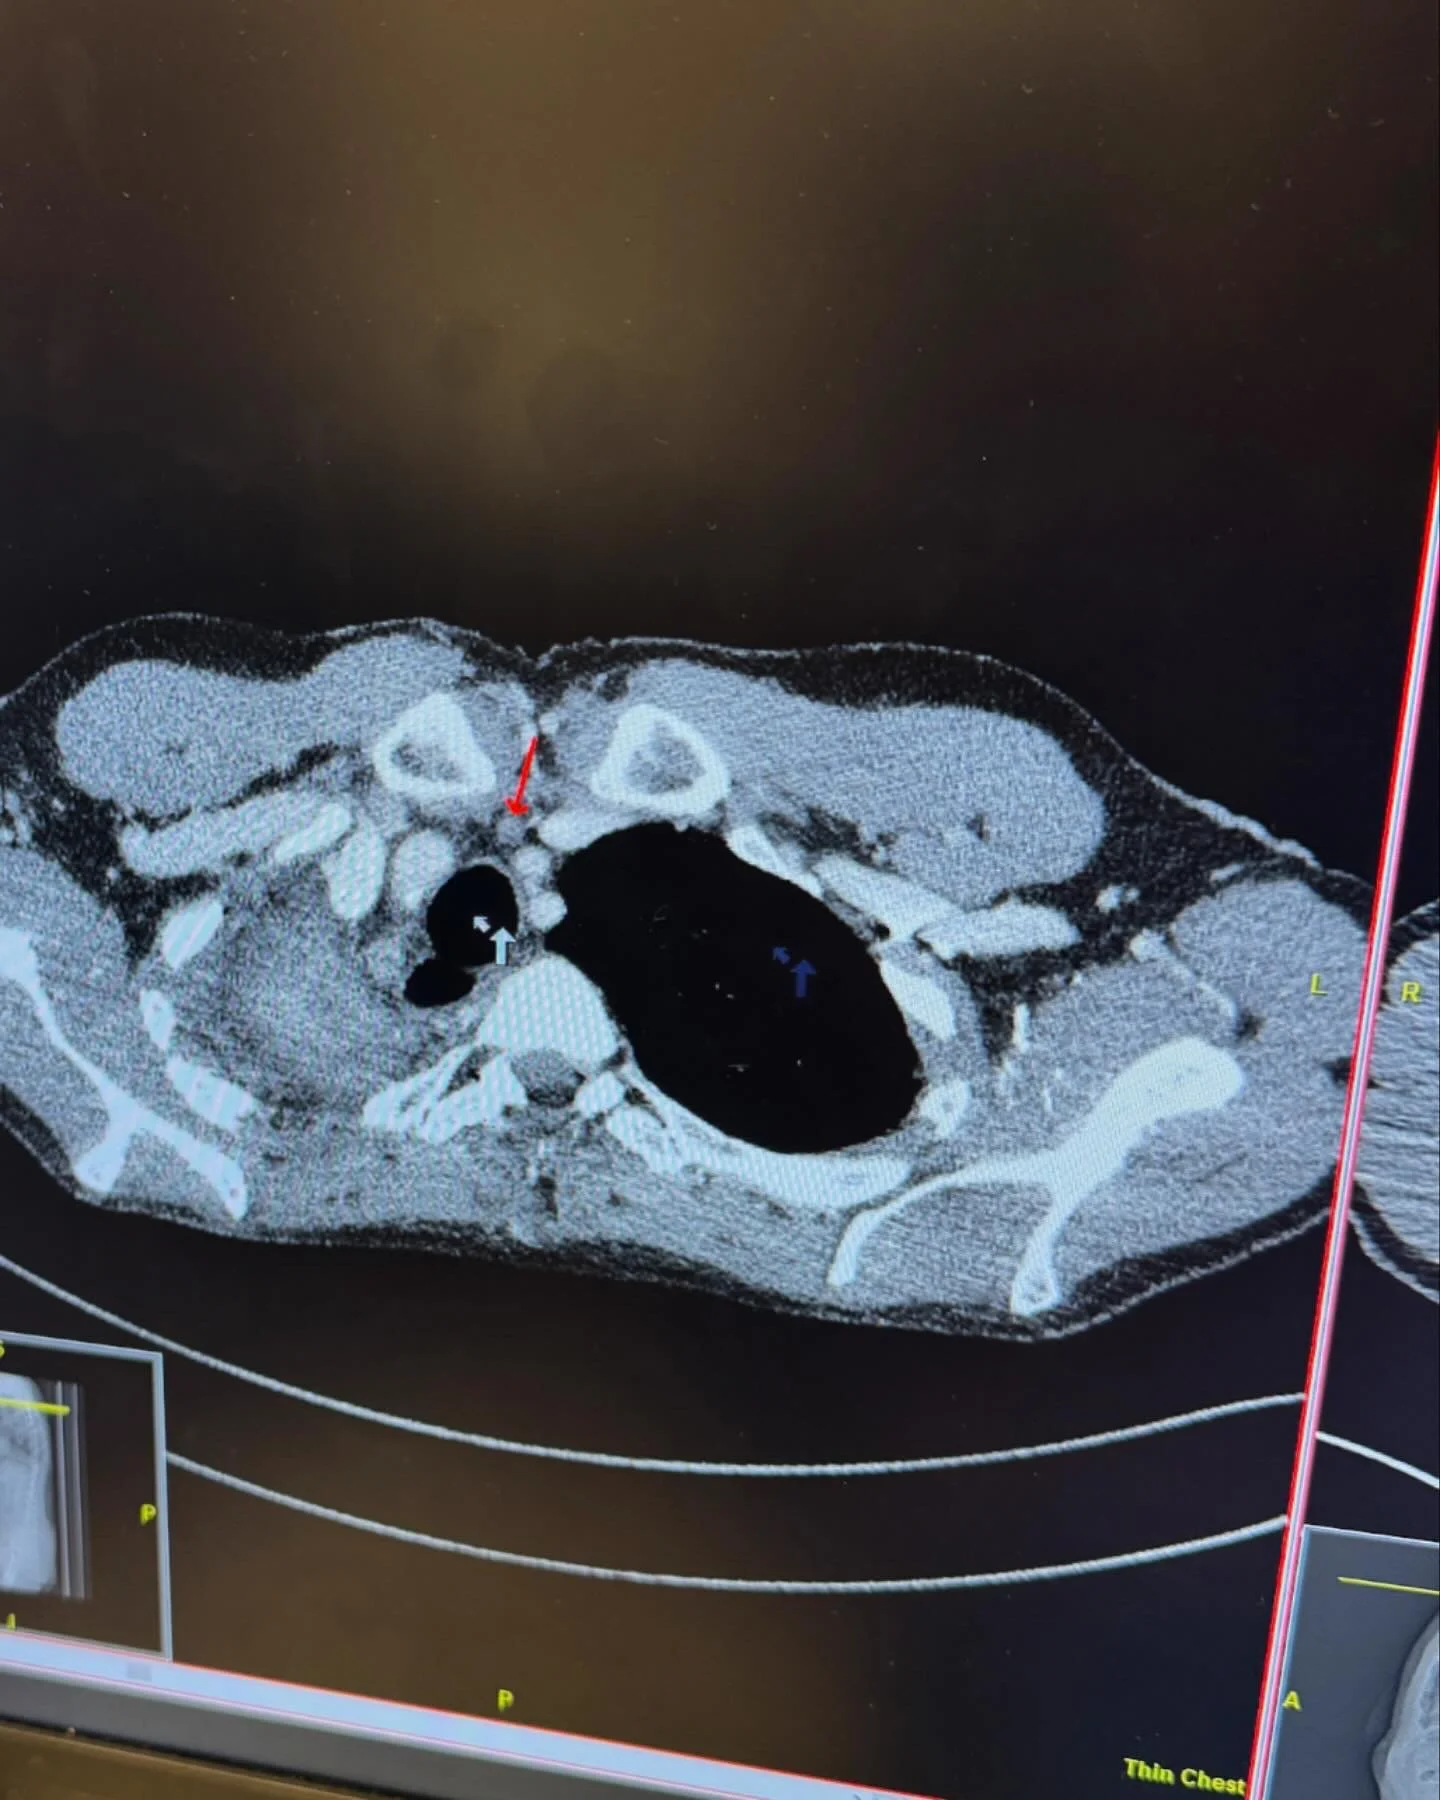

This will be a short update because I know people are busy in the Christmas season. After Mike’s last scans we learned that his treatment of Carboplatin, Pemexetred and Keytruda is not working as well as they had hoped. The MRI results seem pretty stable, but there was small growth in some lung nodules and some lymph nodes that are enlarged in his upper airway. If the treatment was working, all the tumors would be shrinking.

The oncologist ordered a test called “Gardant360” which is a blood test that checks for circulating tumor cells and possible gene mutations. He also brought Mike’s case before the tumor board. They decided that a Broncoscopy would be the best next step, so he had that procedure done at Mayo on Wednesday, December 4th.

We were blessed to have our favorite nurse Ali as Mike’s recovery room nurse. Ali has become a sweet friend since Mike has now had her for three surgeries! They took quite a few pieces of the largest lung tumor, as well as from one of the enlarged lymph node in his upper lung/airway during the biopsy.

Unfortunately, the lymph node did show cancer cells in it which wasn’t really surprising to us, but it was another punch in the gut. Yesterday the results from the Gardant360 test came back showing the original RET gene but no other gene mutations….another punch in the gut!!!